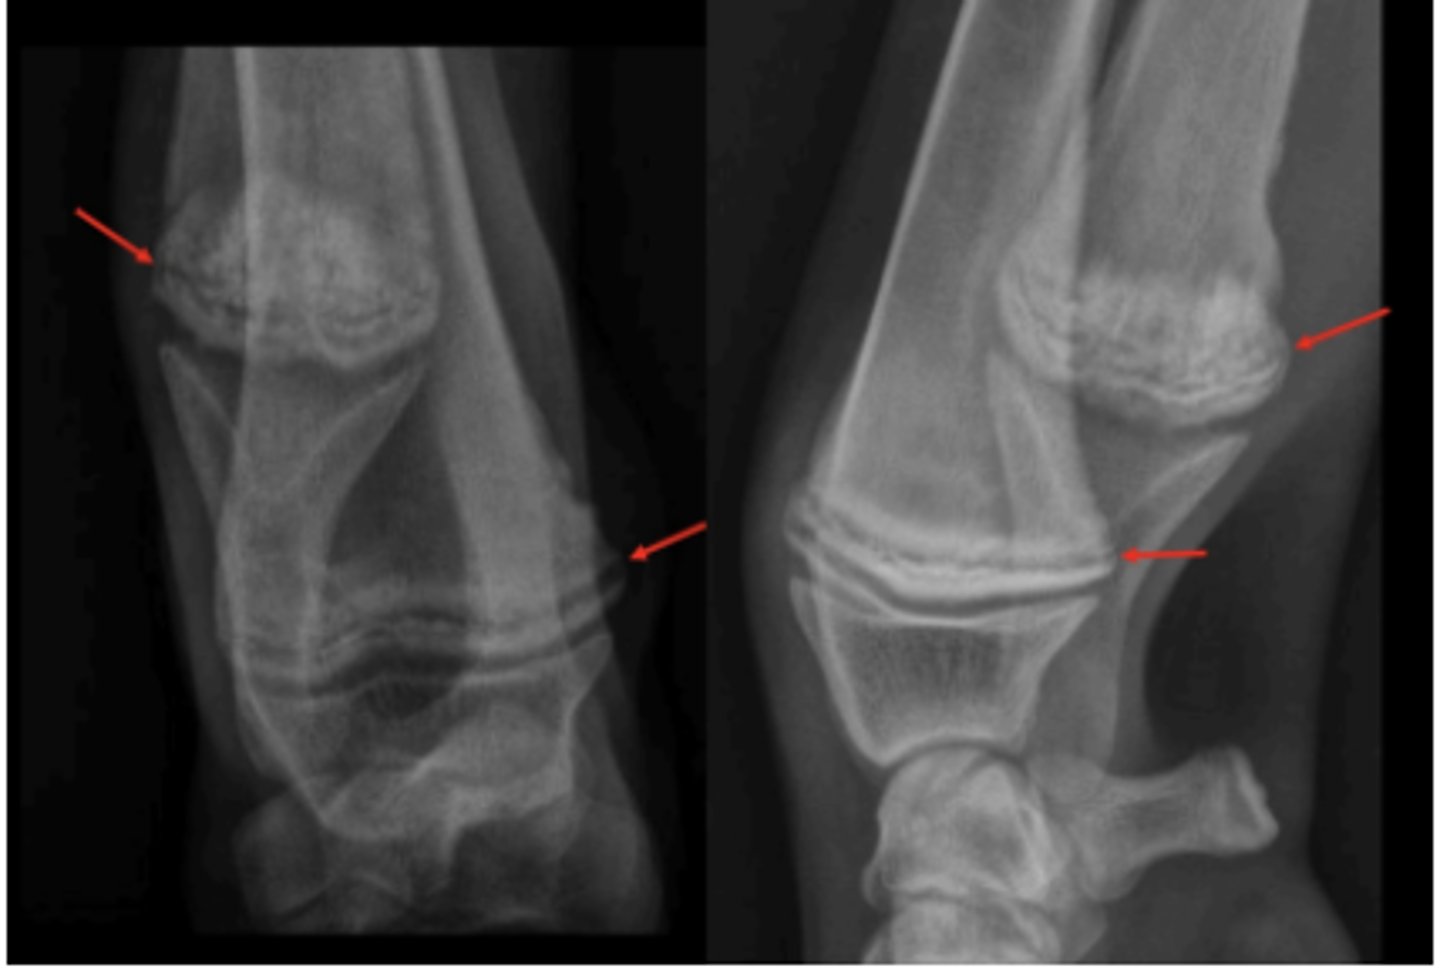

OCD in distal tibia

2 yo horse w talocrural joint effusion; left hock lesion